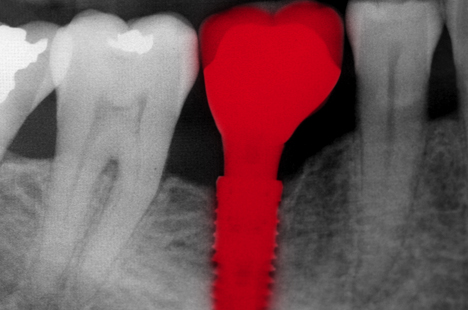

Un implant dentaire, c’est quoi?

Un implant dentaire est une racine artificielle — une vis en titane ou en zircone — insérée dans l’os alvéolaire pour remplacer une dent absente. Coûteuse, l’intervention a l’avantage de bénéficier d’excellents taux de réussite à long terme. En Europe, 4 millions d’implants sont vendus chaque année.